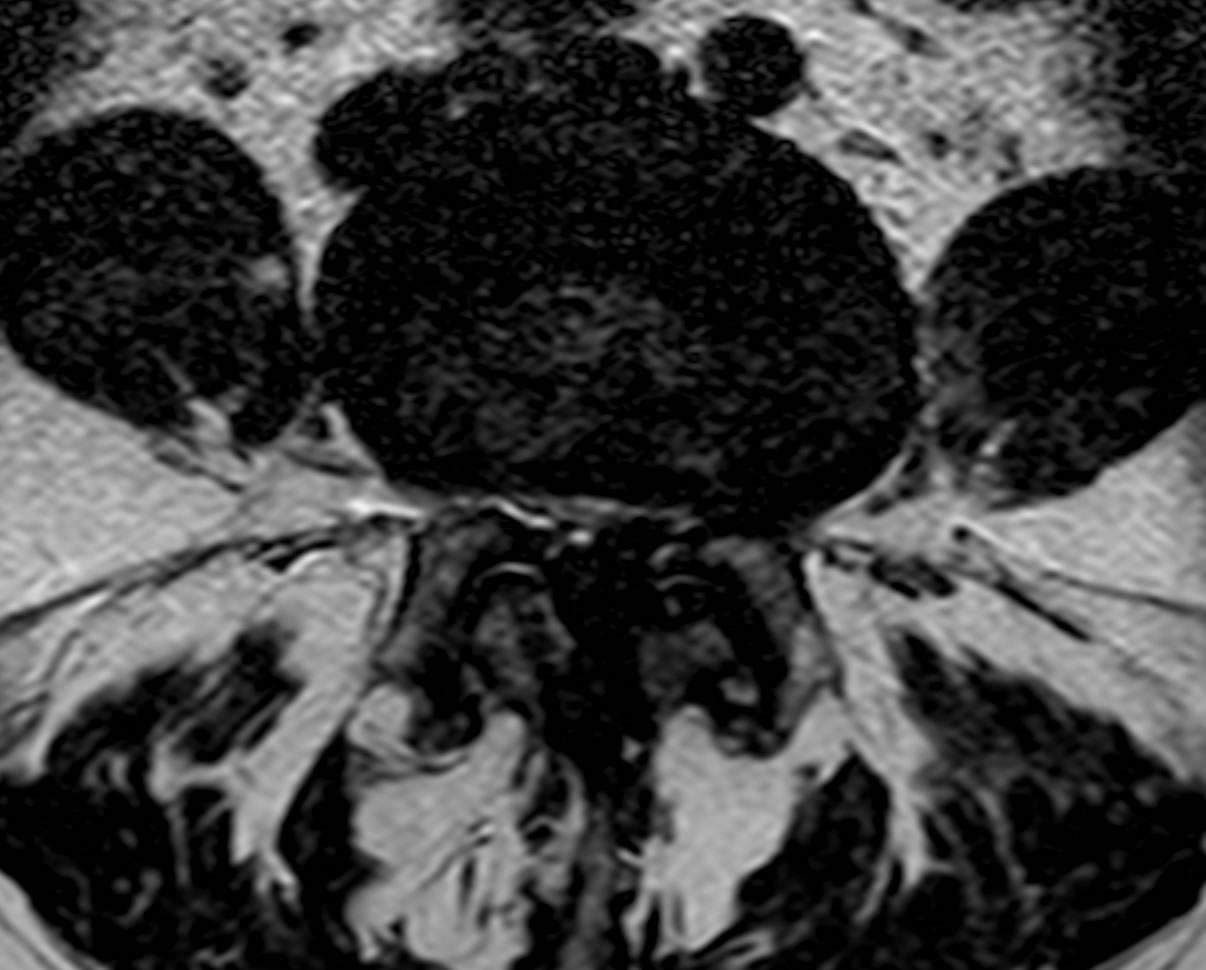

L'investigation principale est l'IRM lombaire ce qui permet au mieux d'apprécier le ou les niveaux responçable de la symptômatologie.

La séquence ci-dessous montre une l'image IRM d'un canal très étroit au niveau L4-L5, on voit qu'il se rétréci très fortement ne laissant quasiement pas de place pour les nerfs de la queue de cheval